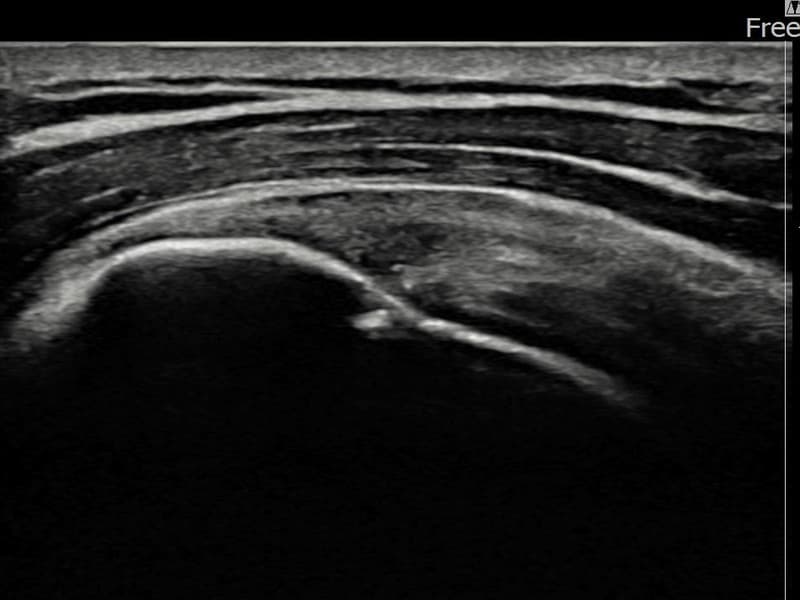

术后

术前超声确认左侧 冈上肌腱 附着部部分撕裂,左侧冈上肌腱回声不连续伴肌腱缺损(9mm × 4mm (肌腱厚度约38%缺损))。术后超声显示撕裂部位充满再生组织,肌腱连续性恢复,回声模式正常化。